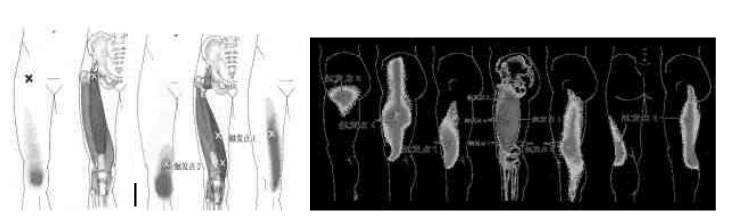

图1. 股直肌、股内側肌、股外侧肌肌筋膜触发点好发部位和它们的牵涉痛区及牵涉到膝关节的位置;股中间肌很少引起膝关节疼痛这里不显图。

3.1 股四头肌群肌筋膜疼痛触发点位置(图1)

图2. 股内收肌群(股内收长肌、短肌和大肌)、股薄肌和缝匠肌触发点好发位置部位和它们的牵涉痛区及牵涉到膝关节的位置。

3.2 股内收肌群、股薄肌和缝匠肌肌筋膜疼痛触发点位置(图2)

3.3 腘绳肌群、腘肌和跖肌肌筋膜

腘绳肌群 腘肌 跖肌 腓侧付韧带

图3. 腘绳肌群、(股二头肌、半腱肌和半膜肌)、腘肌、跖肌和腓侧付韧带触发点好发部位和它们的牵涉痛区及牵涉到膝关节的位置。

疼痛触发点、腓侧付韧带触发点位置(图3)

图4. 小腿三头肌(腓肠肌和比目鱼肌)、阔筋膜张肌肌触发点好发位置和它们的牵涉痛区及牵涉到膝关节的位置。注意:比目鱼肌的触发点可以引起同侧腰骶部的牵涉痛。

3.4 小腿三头肌、阔筋膜张肌肌筋膜疼痛触发点位置(图4)

8例病例,(其中7例田径优秀运动员,年龄18-22岁:4例中长跑,一例跳高,2例短跑;其中一例非专业喜爱运动的人员,34岁);。主诉:一腿跟腱部位疼痛,无法参加强度训练一年。现病史:患者无明原因的一腿跟腱疼痛,有时伴有踝关节周围疼痛,特别在强度训练加重;因此,无法参加各种赛事;造成了运动员和教练的苦恼。后经各种医生诊治,都无改善。专家会诊建议手术探察。患者不愿手术治疗,而到我院门诊就诊。检查:患侧跟腱局部皮肤发黑(据说:是因局部中药熏蒸、针灸和按摩之故,甚至局部封闭),局部仅有压痛,踝关节无肿胀,无明显压痛。但小腿后部肌肉多处有明显压痛,压痛部位可触及条索状结节和痉挛肌纤维。足背屈时患侧关节活动较健侧小。X和MRI影像资料未见异常。因此,按照肌筋膜触发点疼痛的诊断要点[1,2],考虑跟腱痛的初步诊断为:部分小腿肌的肌筋膜触发点疼痛综合症,包括了:胫后肌、胫前肌、腓骨长肌、腓骨短肌、腓肠肌内侧头以及比目鱼肌(图1)。根据诊断,采用湿针穿刺+受累肌牵张+药物辅助的综合性疗法对患者进行试探性治疗。

图1. 常见引起运动员跟腱牵涉疼痛的小腿后部肌肉疼痛触发点的位置。A示胫前肌;B示比目鱼肌;C示腓肠肌。